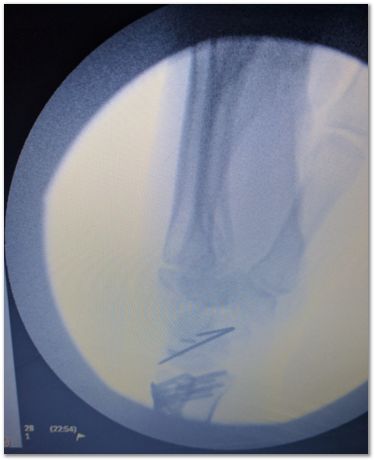

The wire seen is temporary to hold things in place during surgery. X-ray.